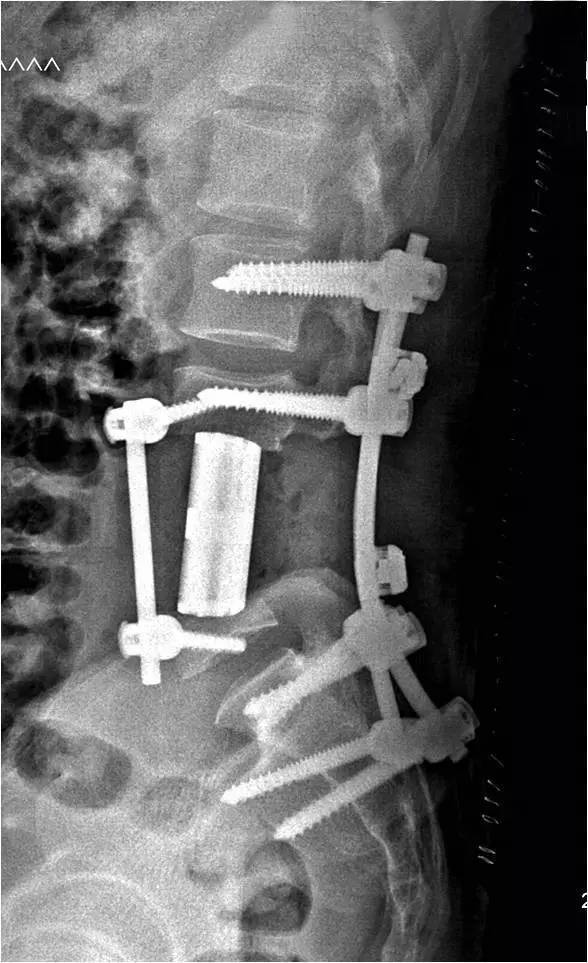

手术在省骨科研究院院长金大地教授的指导下,从早上8点一直做到晚上8点,整整12个小时。手术切除了患者第4节腰椎与第3节、第5节各半节椎体,总共长达9厘米,并植入了同样尺寸的3D打印人工椎体。该次手术由李浩淼率领骨肿瘤科团队,联合血管外科、普外科、泌尿外科等多学科完成。

3D打印换脊骨图片

术后检查显示,患者体内的3D打印人工椎体匹配良好,人工椎体两端弧形设计与上下椎体终板贴敷可靠。患者术后恢复良好,术后两周就可下地行走,并于近日出院。